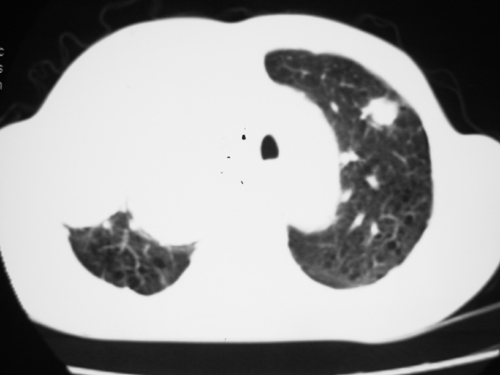

以下是引用yangyudong333在2008-4-29 5:46:00的发言:[br]1左上叶结节呈分叶状,边缘毛刺,考虑肺癌并纵隔淋巴结转移可能性大,结核待排,[br] [br]2右侧多发包裹性胸腔积液

以下是引用zsl6918在2008-4-29 9:15:00的发言:[br]右侧包裹性积液穿刺术后改变,肺内多发结节不除外转移可能。建议查胸水,问病史。